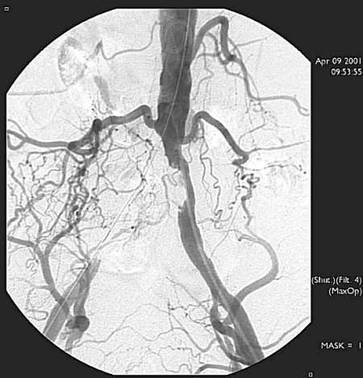

Ocluzia arterei iliace primitive drepte si stenoza arterei iliace primitive

stangi

Arteriografie.

Colaterale bogate (hipertrofie de artere lombare).

Reinjectarea portiunii distale a arterei iliace primitive drepte in amonte de

bifurcata iliacei.